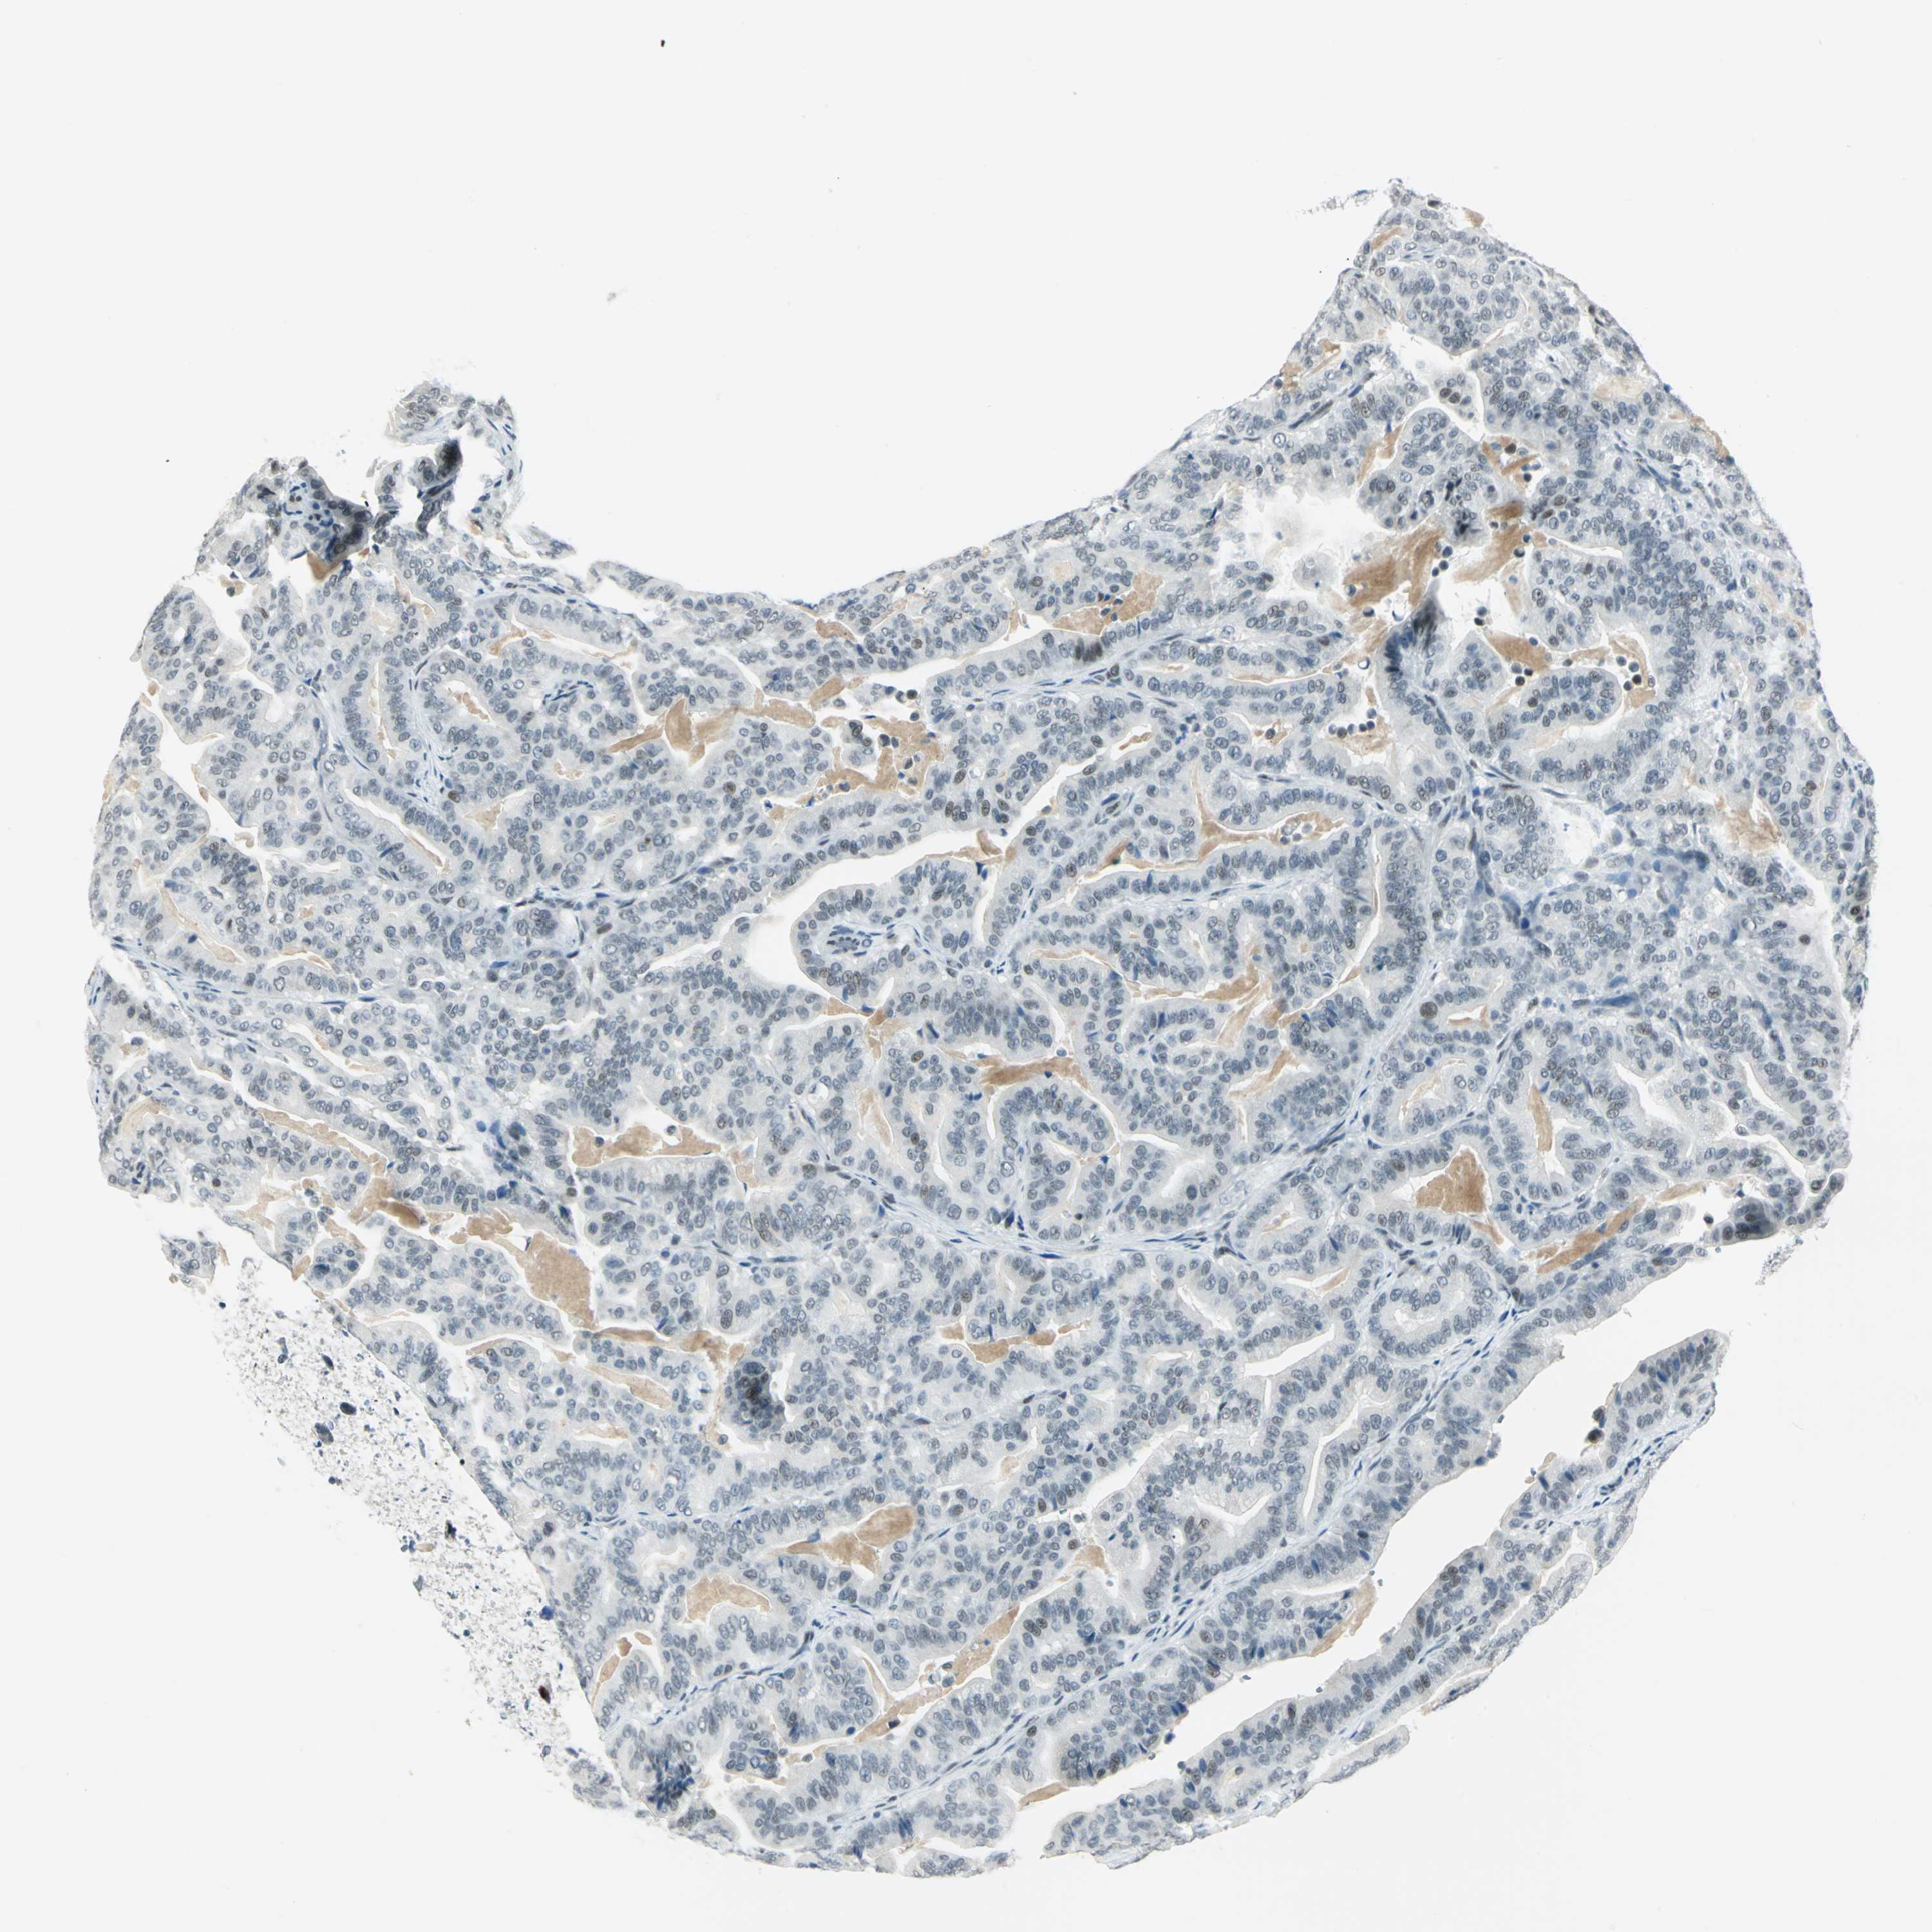

PANCREATIC CANCER - Protein expressioni

A mouse-over function shows sample information and annotation data. Click on an image to view it in a full screen mode. Samples can be filtered based on level of antibody staining by selecting one or several of the following categories: high, medium, low and not detected. The assay and annotation is described here.

Note that samples used for immunohistochemistry by the Human Protein Atlas do not correspond to samples in the TCGA dataset.

Antibody stainingi

Antibody staining in the annotated cell types in the current human tissue is reported as not detected, low, medium, or high, based on conventional immunohistochemistry profiling in selected tissues. This score is based on the combination of the staining intensity and fraction of stained cells.

Each image is clickable and will lead to virtual microscopy that enables deeper exploration of all samples and also displays staining intensity scores, fraction scores and subcellular localization as well as patient and tissue information for each sample.

Antibody HPA006081

Staining

High

Medium

Low

Not detected

Intensity

Strong

Moderate

Weak

Negative

Quantity

>75%

75%-25%

<25%

None

Location

Nuclear

Cytoplasmic/membranous

Cytoplasmic/membranous,nuclear

Adenocarcinoma, NOS

Adenocarcinoma, metastatic, NOS